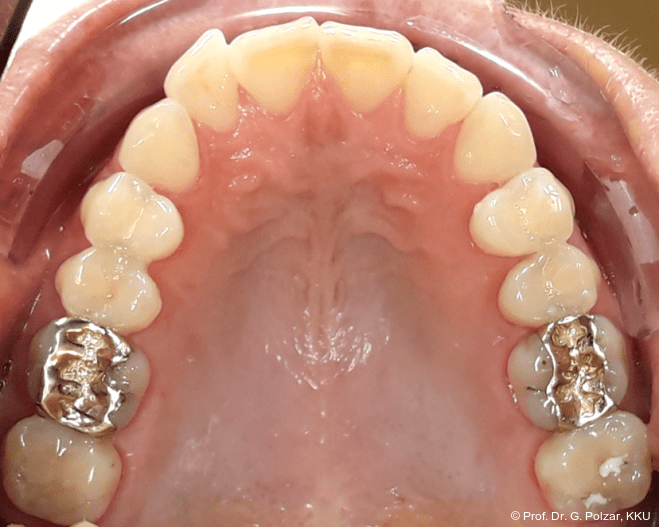

Der intraorale Befund zeigte eine scheinbar neutrale Verzahnung. Trotz Lingualretainer in der UK-Front war ein Engstand in der Unterkieferfront mit leichter Protrusion erkennbar. Appro­ximal des Zahnes 41 waren deutliche schwarze Dreiecke zu erkennen, zudem wies der Zahn eine leichte gingivale Rezession auf (Abb. 3a–f).

Nach weiteren acht Monaten Aligner-Therapie zur postoperativen Feineinstellung konnte die aktive Therapie weitgehend abgeschlossen werden. Mit einem CaseRefinement wurden die verbliebenen frontalen Lücken geschlossen (Abb. 17a–e).